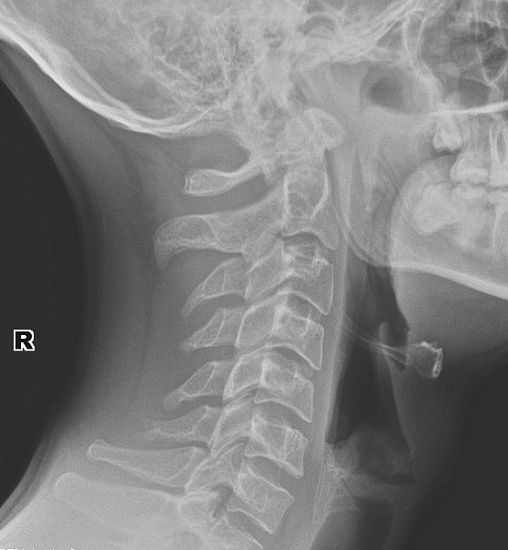

Рентгенография гортани в боковой проекции

Рентгенография гортани в боковой проекции (по Земцову) – важный метод прицельного исследования, который позволяет оценить состояние гортано-глотки. Диагностическая услуга выполняется одной проекции.

Исследование позволяет выявить сужение просвета гортани различной этиологии: опухолевой, инфекционной, инородные тела.